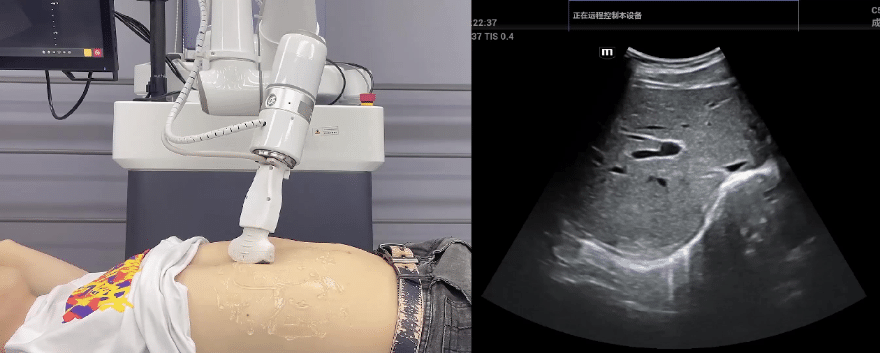

milan.米兰中国协作机器人搭载库柏特自主研发的机器人遥操作、多模态数据采集与处理、机器人模仿学习、机器人力位控制等技术升级变革传统超声,可实现远程+自主超声扫查与诊断,从传统远程超声仅能对话会诊变革升级为能对话、能操作,使得基层患者可就近享受异地三甲专家扫诊服务。实现专家端与患者端远程连接,并支持专家端与多路患者端自由切换控制。

EC66协作机器人末端可搭载主流品牌高品质超声仪,让操作指令和影像低延迟、高精准、高保真传输,确保检查可靠、医患放心;智能力控等三重防护系统,确保患者舒适、安全。

milan.米兰中国协作机器人与超声深度打通,最大程度保留医生左右手同时操作传统超声的习惯,并改善其舒适性,超声检查实际应用场景展示如下: